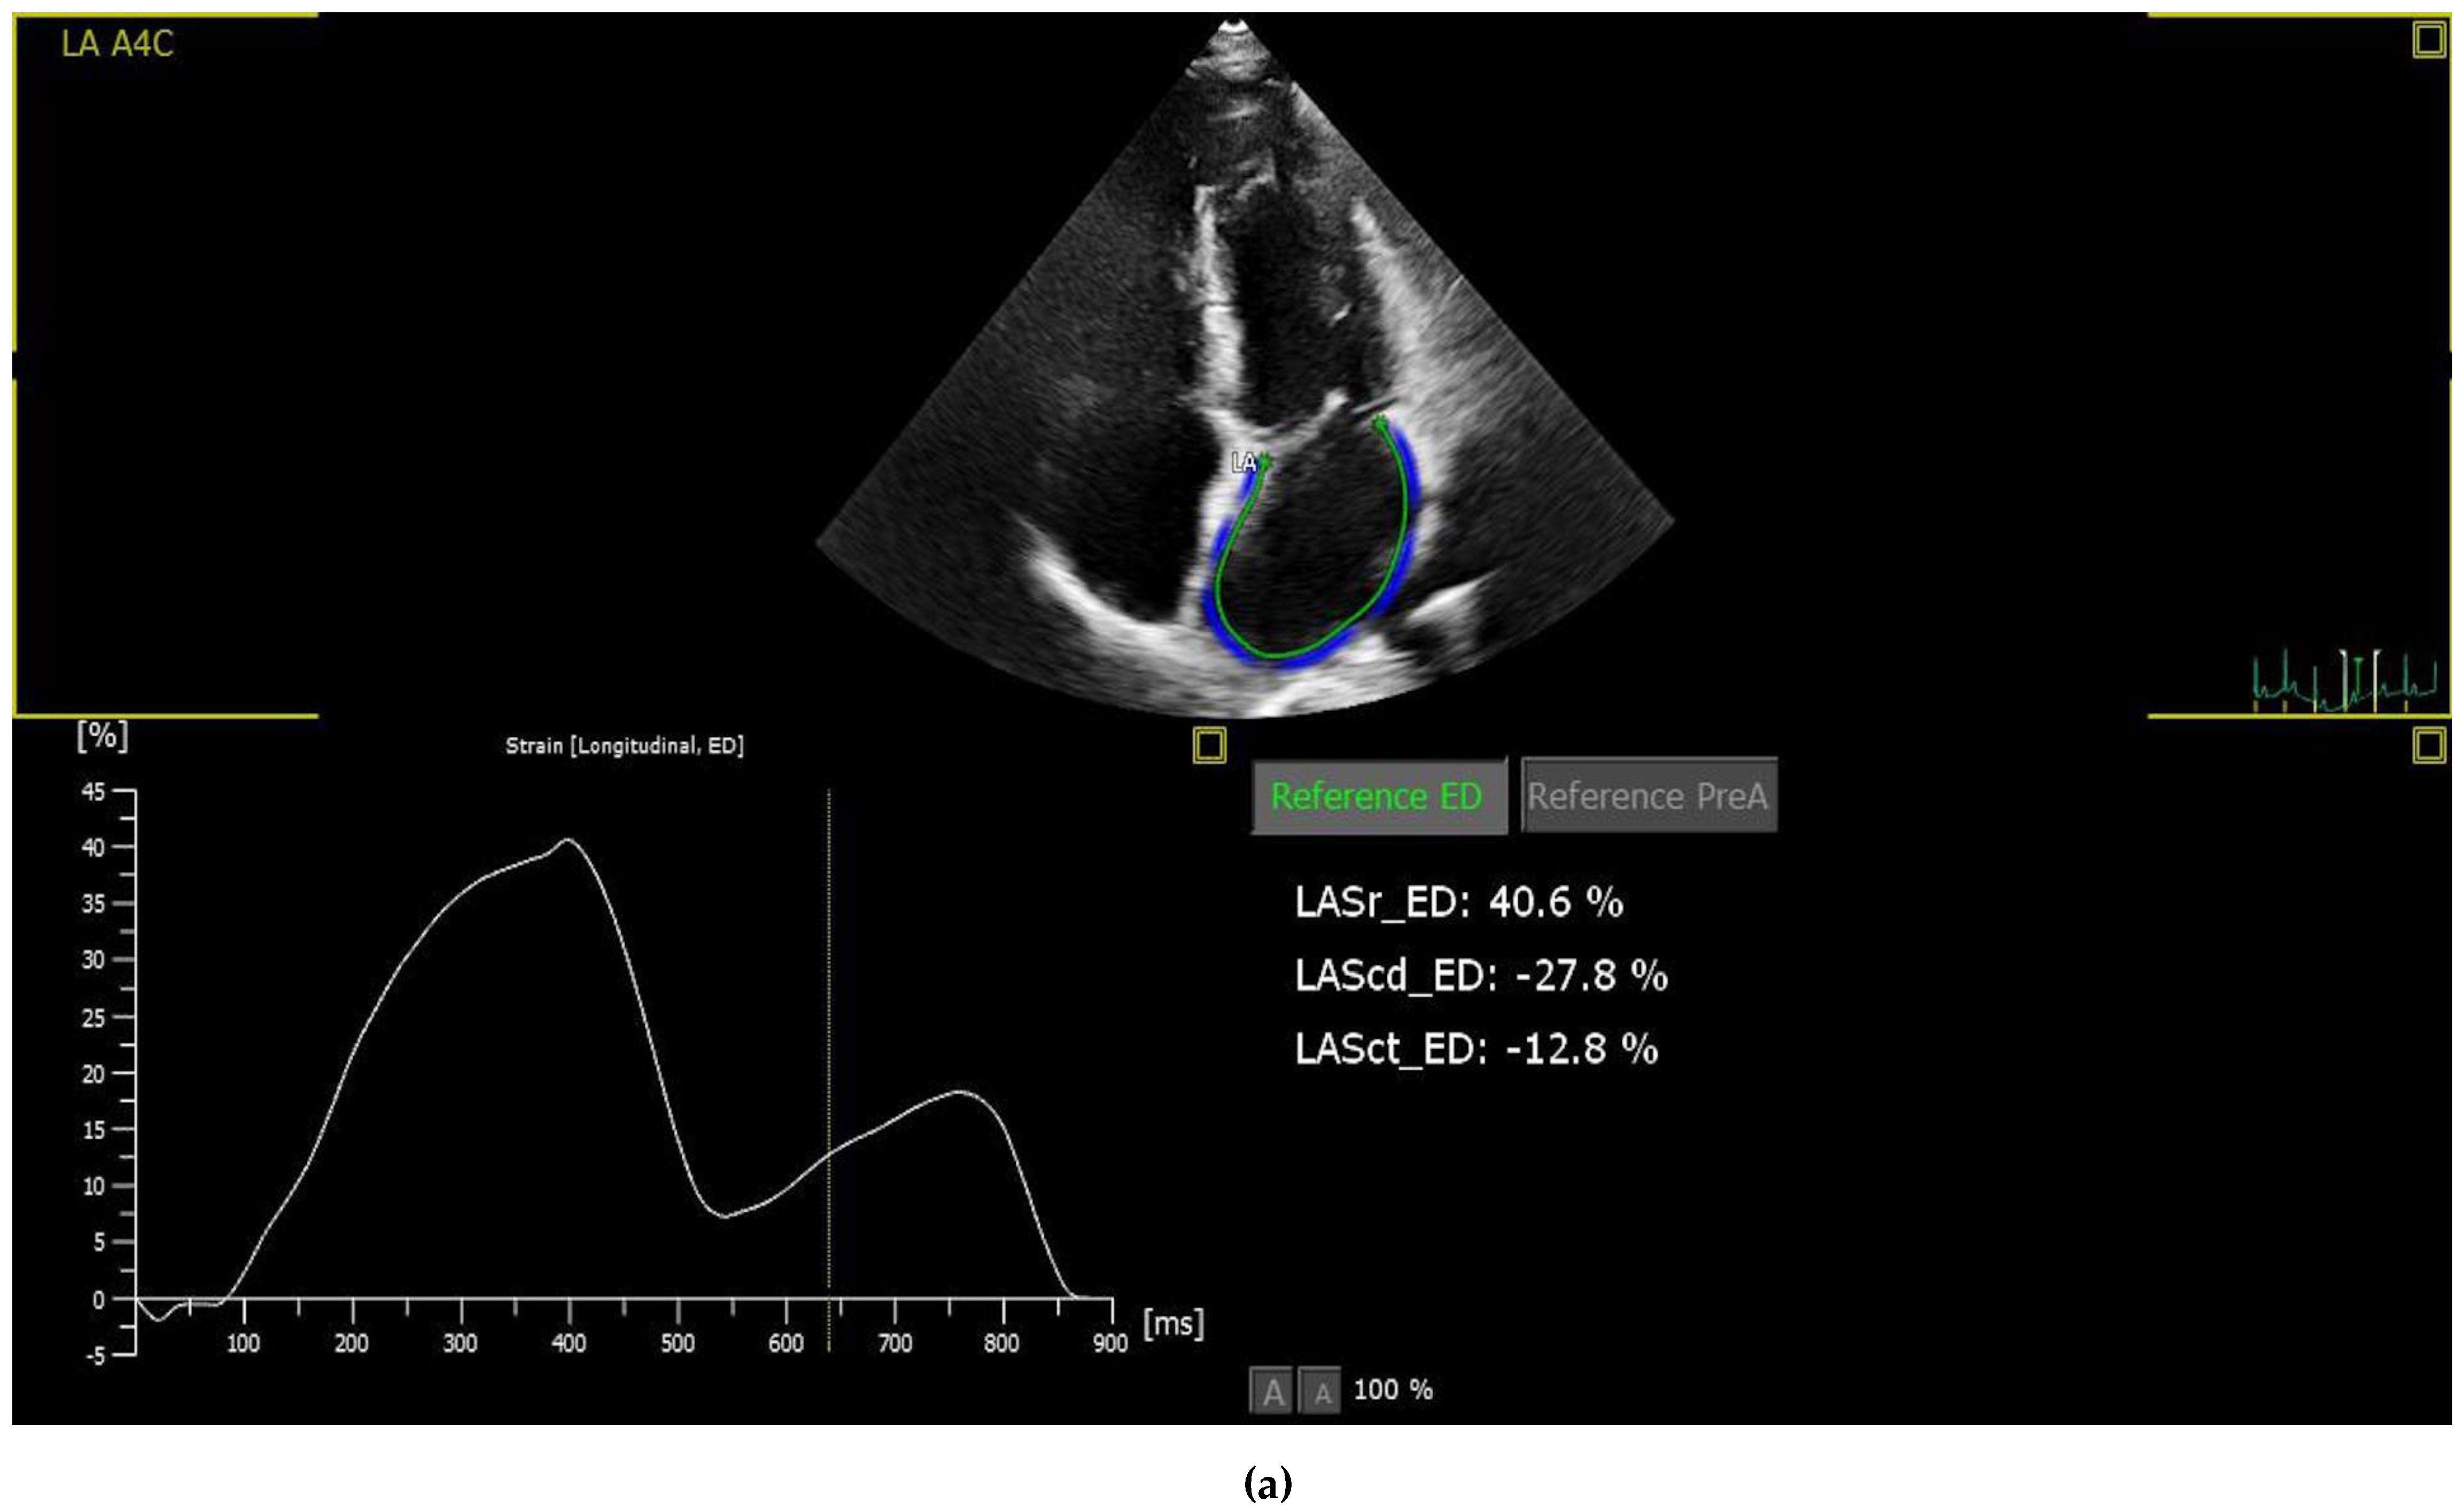

Patients with suboptimal image quality for strain analysis were excluded from the study. The echocardiographic images were analysed by a cardiologist who is particularly interested and trained in cardiovascular imaging and strain echocardiography. The strain values, including the right ventricle GLS (RVGLS) and right ventricle free wall strain (RV-FWSL), the LVGLS, and components of the LAS (atrial reservoir (LAS-r), conduit (LAS-cd), and contractile (LAS-ct) function), were examined from the stored echocardiographic images using a commercially available workstation (QLAB version 13) and by following the recommendations of the EACVI [13] (Figure 1).

Figure 1.

Imaging of STE components of left atrial (a), left ventricle (b) and right ventricle strain (c). Abbreviations: LA: Left atrium, A4C: Apikal four chamber, LASr: Left atrial reservoir strain, LAScd: left atrium conduit strain, LASct: left atrium contractile strain, A2C:Apikal two chamber, A3C:Apikal three chamber, GLS: Global longitudinal strain, Avg: Average, LV: Left ventricle, RVFWSL: Right ventricle free wall strain longitudinal, RV4CSL: Right ventricle four chamber strain longitudinal.